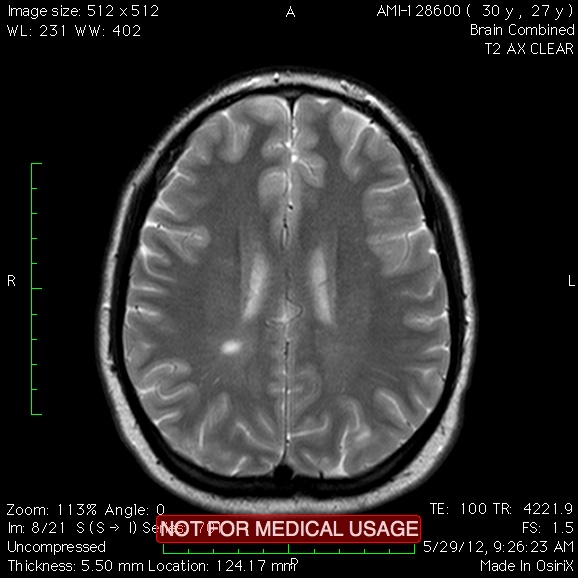

MS is all about the lesions. A lot of people with MS only get a lesion or two and progress very slowly. I am not that lucky. I continue to get new lesions year after year. My first set of MRIs found 10+ lesions on the spinal cord and a few scattered through my brain. That was just the beginning.

I have a hard time when things feel like they are somewhat stable for a few months, yet in reality the lesions continue to progress. Currently my brain and spinal cord are active. These lesions effect things like cognition, spacial awareness, sensory nerves and muscle strength. It is tough to see the cognitive changes when you rely on the brain to tell you whats wrong.